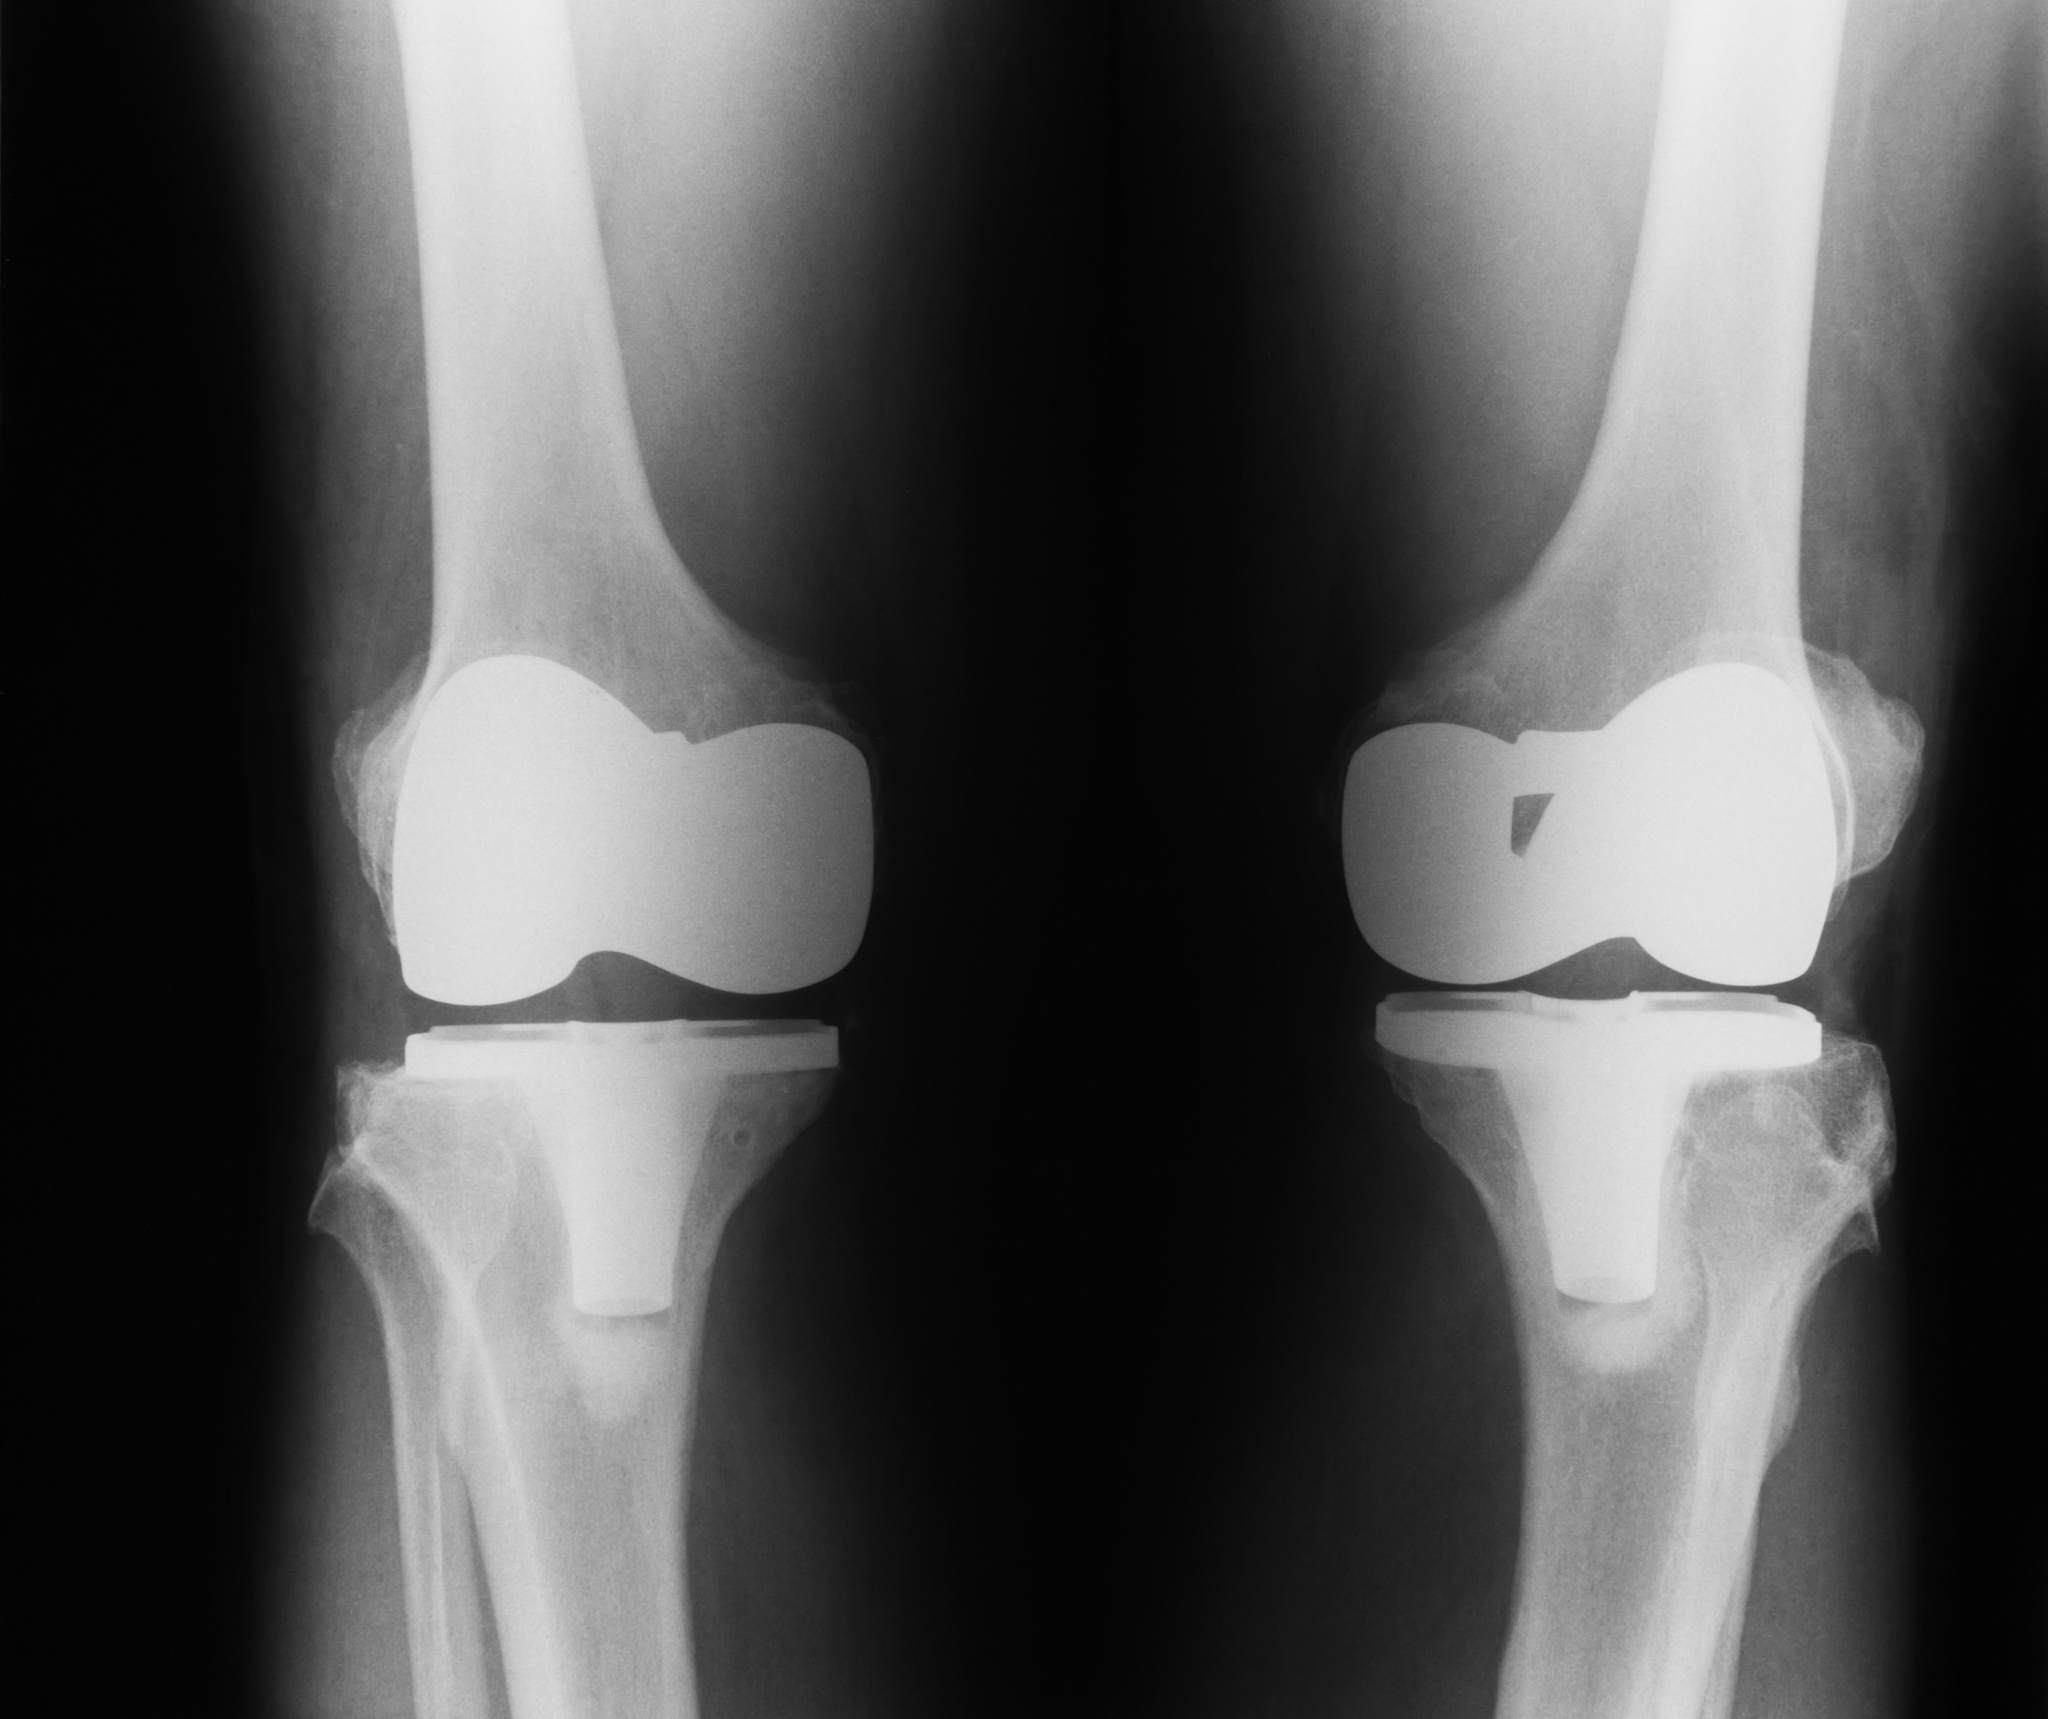

3. 适应症不同:玻璃酸钠适用于轻至中度的骨关节炎,特别是膝关节和髋关节。封闭注射适用于急性或慢性的关节疼痛和炎症,可以用于任何关节。